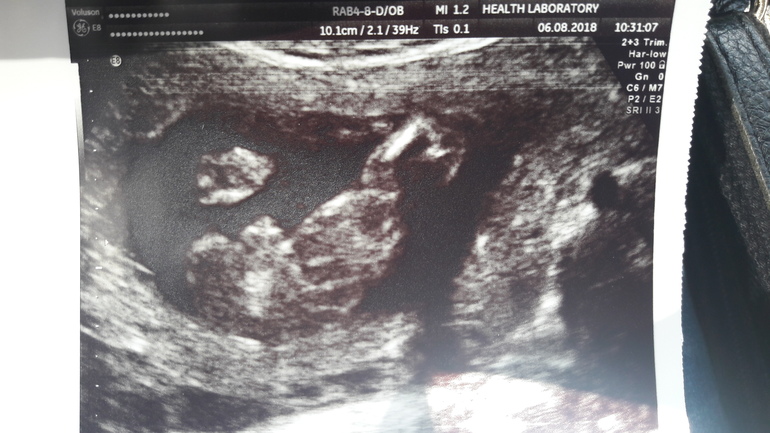

Узи от 6 авг-мальчик

УЗИ, КТГ, доплерПрошли мы 2 скрининг,все хорошо с малышом.Так подрос,такой любимый и ,самое главное ,здоровый))) ииии.... сказали нам,что 100%девочка.Я показала предыдущее фото с двух узи из разных мест,где нам показали мальчика.Разница между узи 10 дней.Меня спросили:а фото точно твое?Говорю мое,видела все в экран.На что мне сказали,что пол узнаю после родов,но сегодня-девочка))))Так не интересно.....